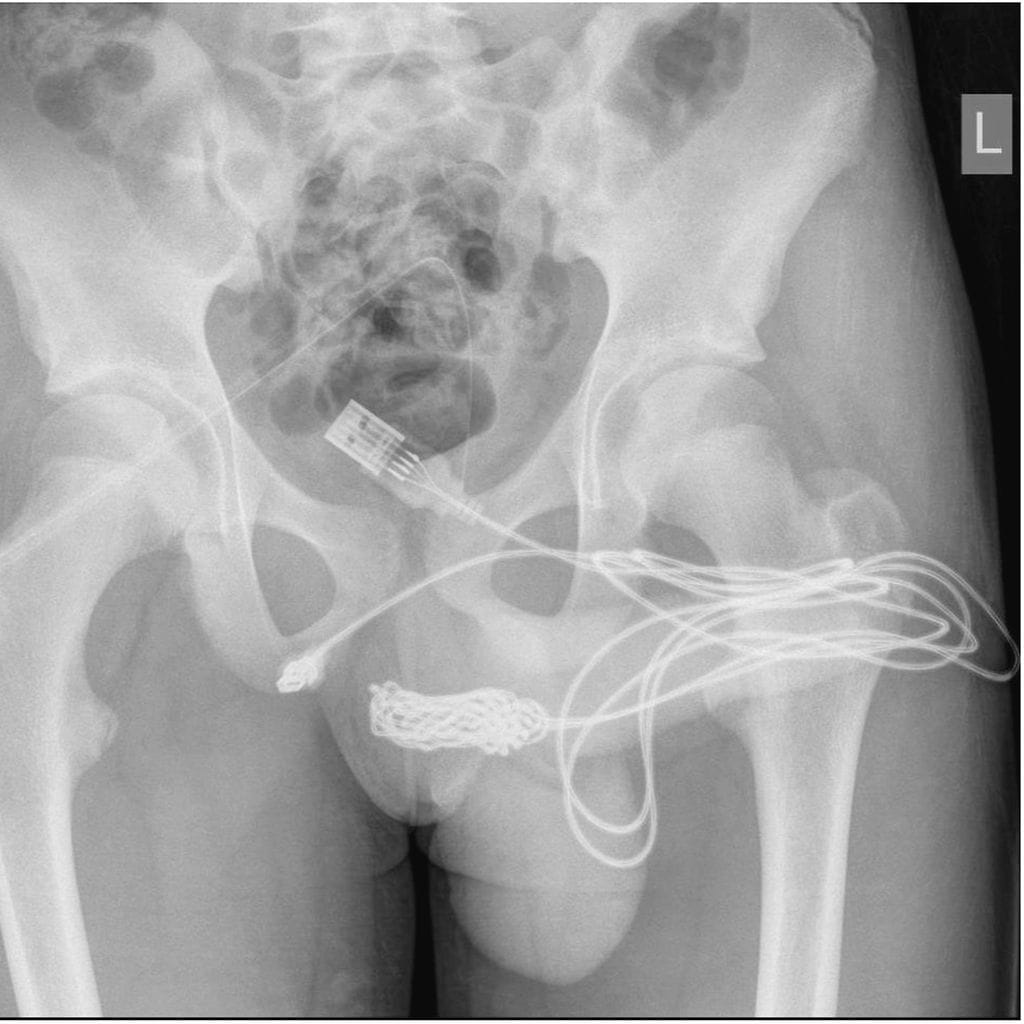

15-vuotias teinipoika työnsi virtsaputkeensa USB-kaapelin mitatakseen peniksensä pituuden sekä samalla tyydyttääkseen itseään. Kokeilu ei päättynyt kovin hyvin, sillä kaapeli jäi jumiin siinä olleen solmun vuoksi.

Poika yritti vetää kaapelia ulos itsestään useita kertoja, mutta lopputuloksena oli vain suuria määriä verta virtsassa. Vanhemmat veivät lapsensa päivystykseen. Kun lääkäritkin epäonnistuivat poistamaan vierasesineen virtsaputkesta, teini kiidätettiin Lontoossa sijaitsevaan yliopistolliseen sairaalaan.

University College Hospitalin lääkärit poistivat USB-kaapelin pojan virtsaputkesta leikkauksessa. Teinin kuntoutuminen lähti hyvin käyntiin, mutta lääkärien mukaan potilaan tilaa on seurattava mahdollisten myöhempien komplikaatioiden varalta.